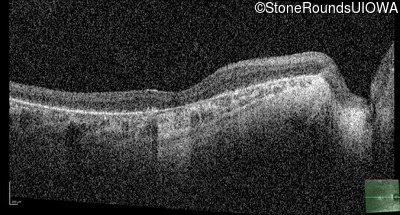

Optical Coherence Tomography - Right - 5/225

Exemplar / OCT Stack